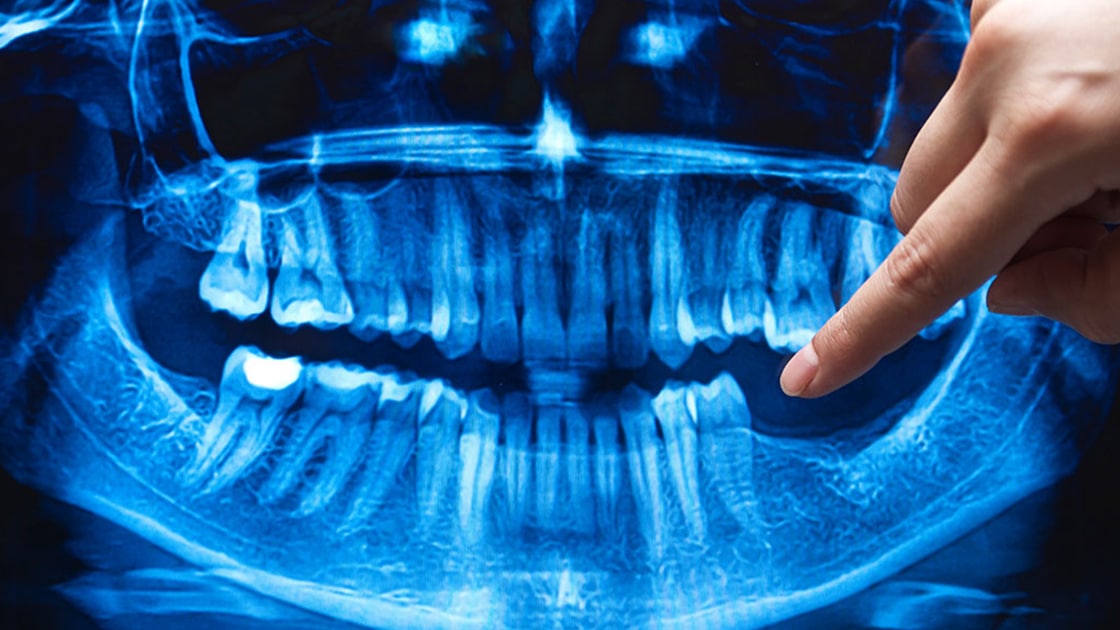

Dental Implants

Dental implants are composed of three pieces: a small screw made of a biocompatible metal called titanium, an abutment that connects the screw, and the final restoration.

Wisdom Tooth Removal (3rd Molars)

Not all wisdom teeth need to be removed, but when determining whether or not to remove one or more third molars, our team will assess the following factors: crowding, jaw size, impaction, and proper occlusion.